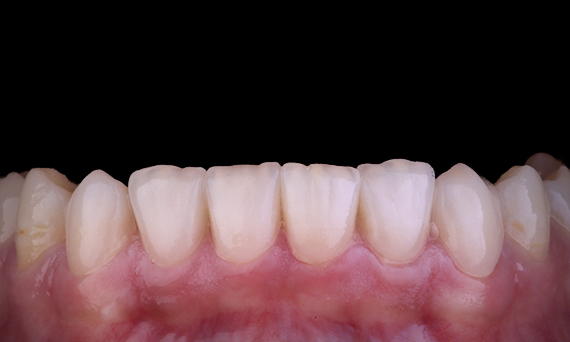

Este paciente se presentó con una restauración rota en el aspecto distal-oclusal de la pieza dental 46. La restauración existente del diente se extendió de manera muy profunda y cerca de la cámara pulpar. Dado el gran tamaño de la restauración, es muy probable que, si simplemente reemplazamos la restauración con otra restauración directa, el resultado sería el mismo, con la restauración rompiendo debajo de las cargas oclusales a las que se someten el diente y la restauración. Por lo tanto, se recomendó una opción indirecta para el diente. Dado que el tercio mesial del diente no se vio afectado en gran medida por el resto de una estructura dental sólida, podríamos preservarlo y ser mínimamente invasivos restaurando el diente con una restauración indirecta con el sistema CEREC

Dr. Sahil Soni, Queensland, Australia